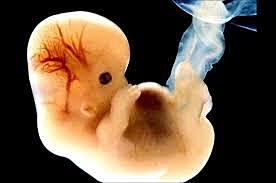

• Semana 5

19

Semana 5

La cabeza crece mucho más que otras regiones. El agrandamiento de la cabeza obedece sobre todo al desarrollo rápido de las prominencias cerebral y facial.

La cara establece contacto con la prominencia cardíaca.

• Semana 6

20

Semana 6

los brazos y las piernas se han alargado y se pueden distinguir las áreas de los pies y de las manos

las manos y los pies tienen dedos (dígitos), pero pueden aún estar adheridos por membranas

el cerebro continúa formándose

comienza la formación de los pulmon